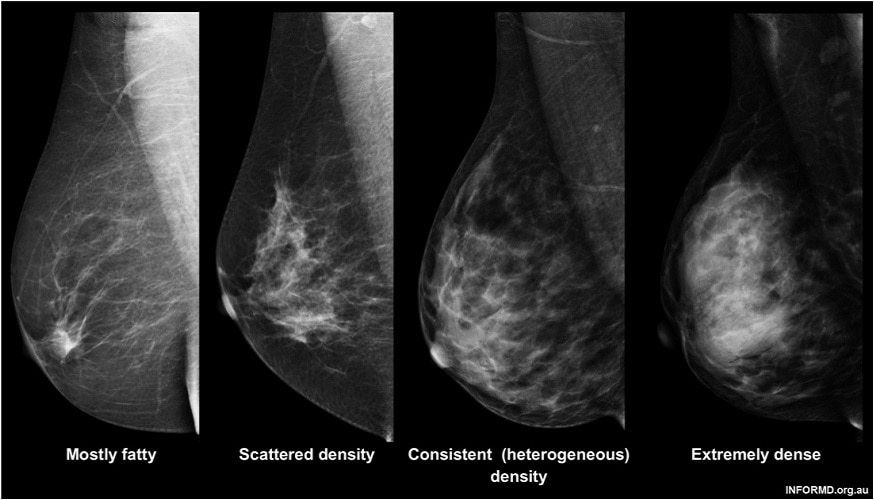

Know the facts, bust myths and keep yourself informed about breast density and its impacts on your health